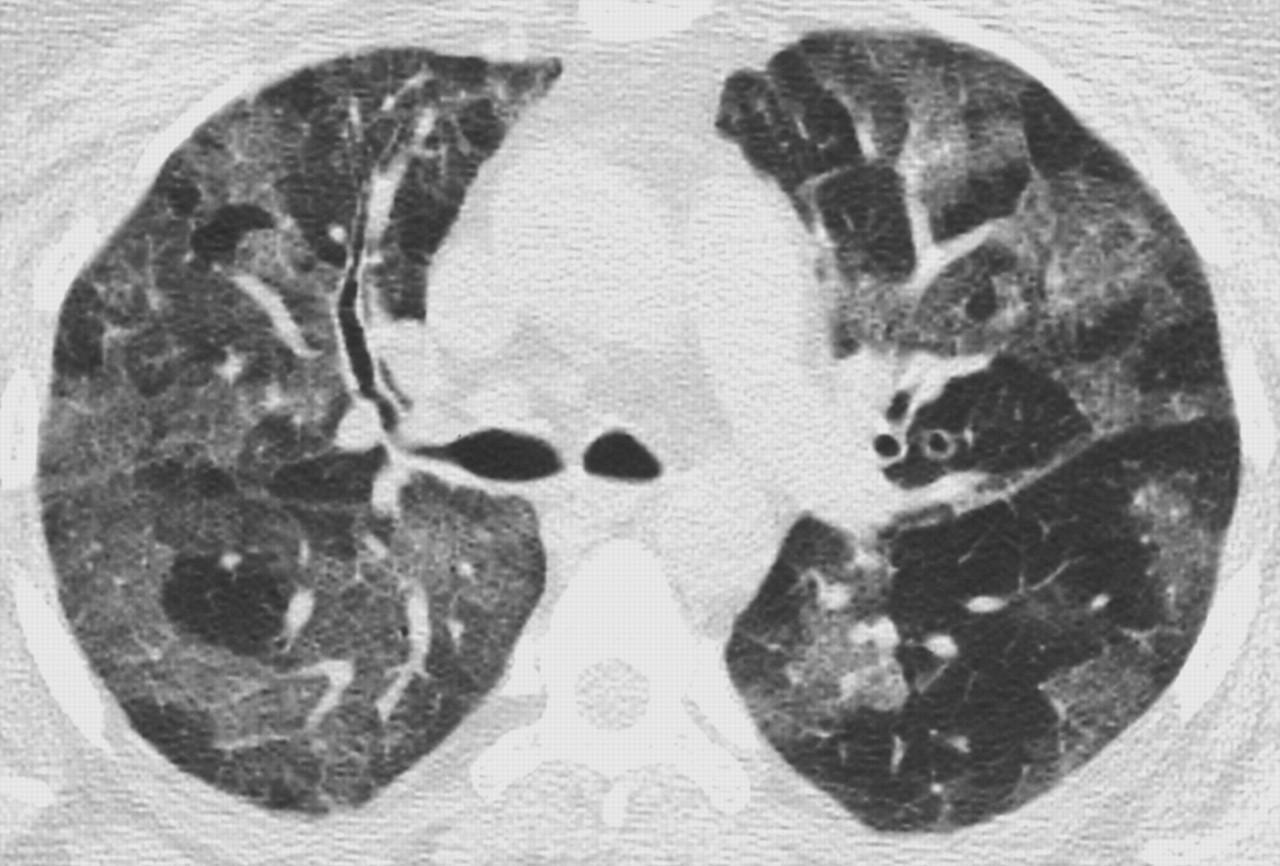

Визуализация и диагностика неинвазивного аспергиллеза с помощью КТ

Раздел: Необычные решения